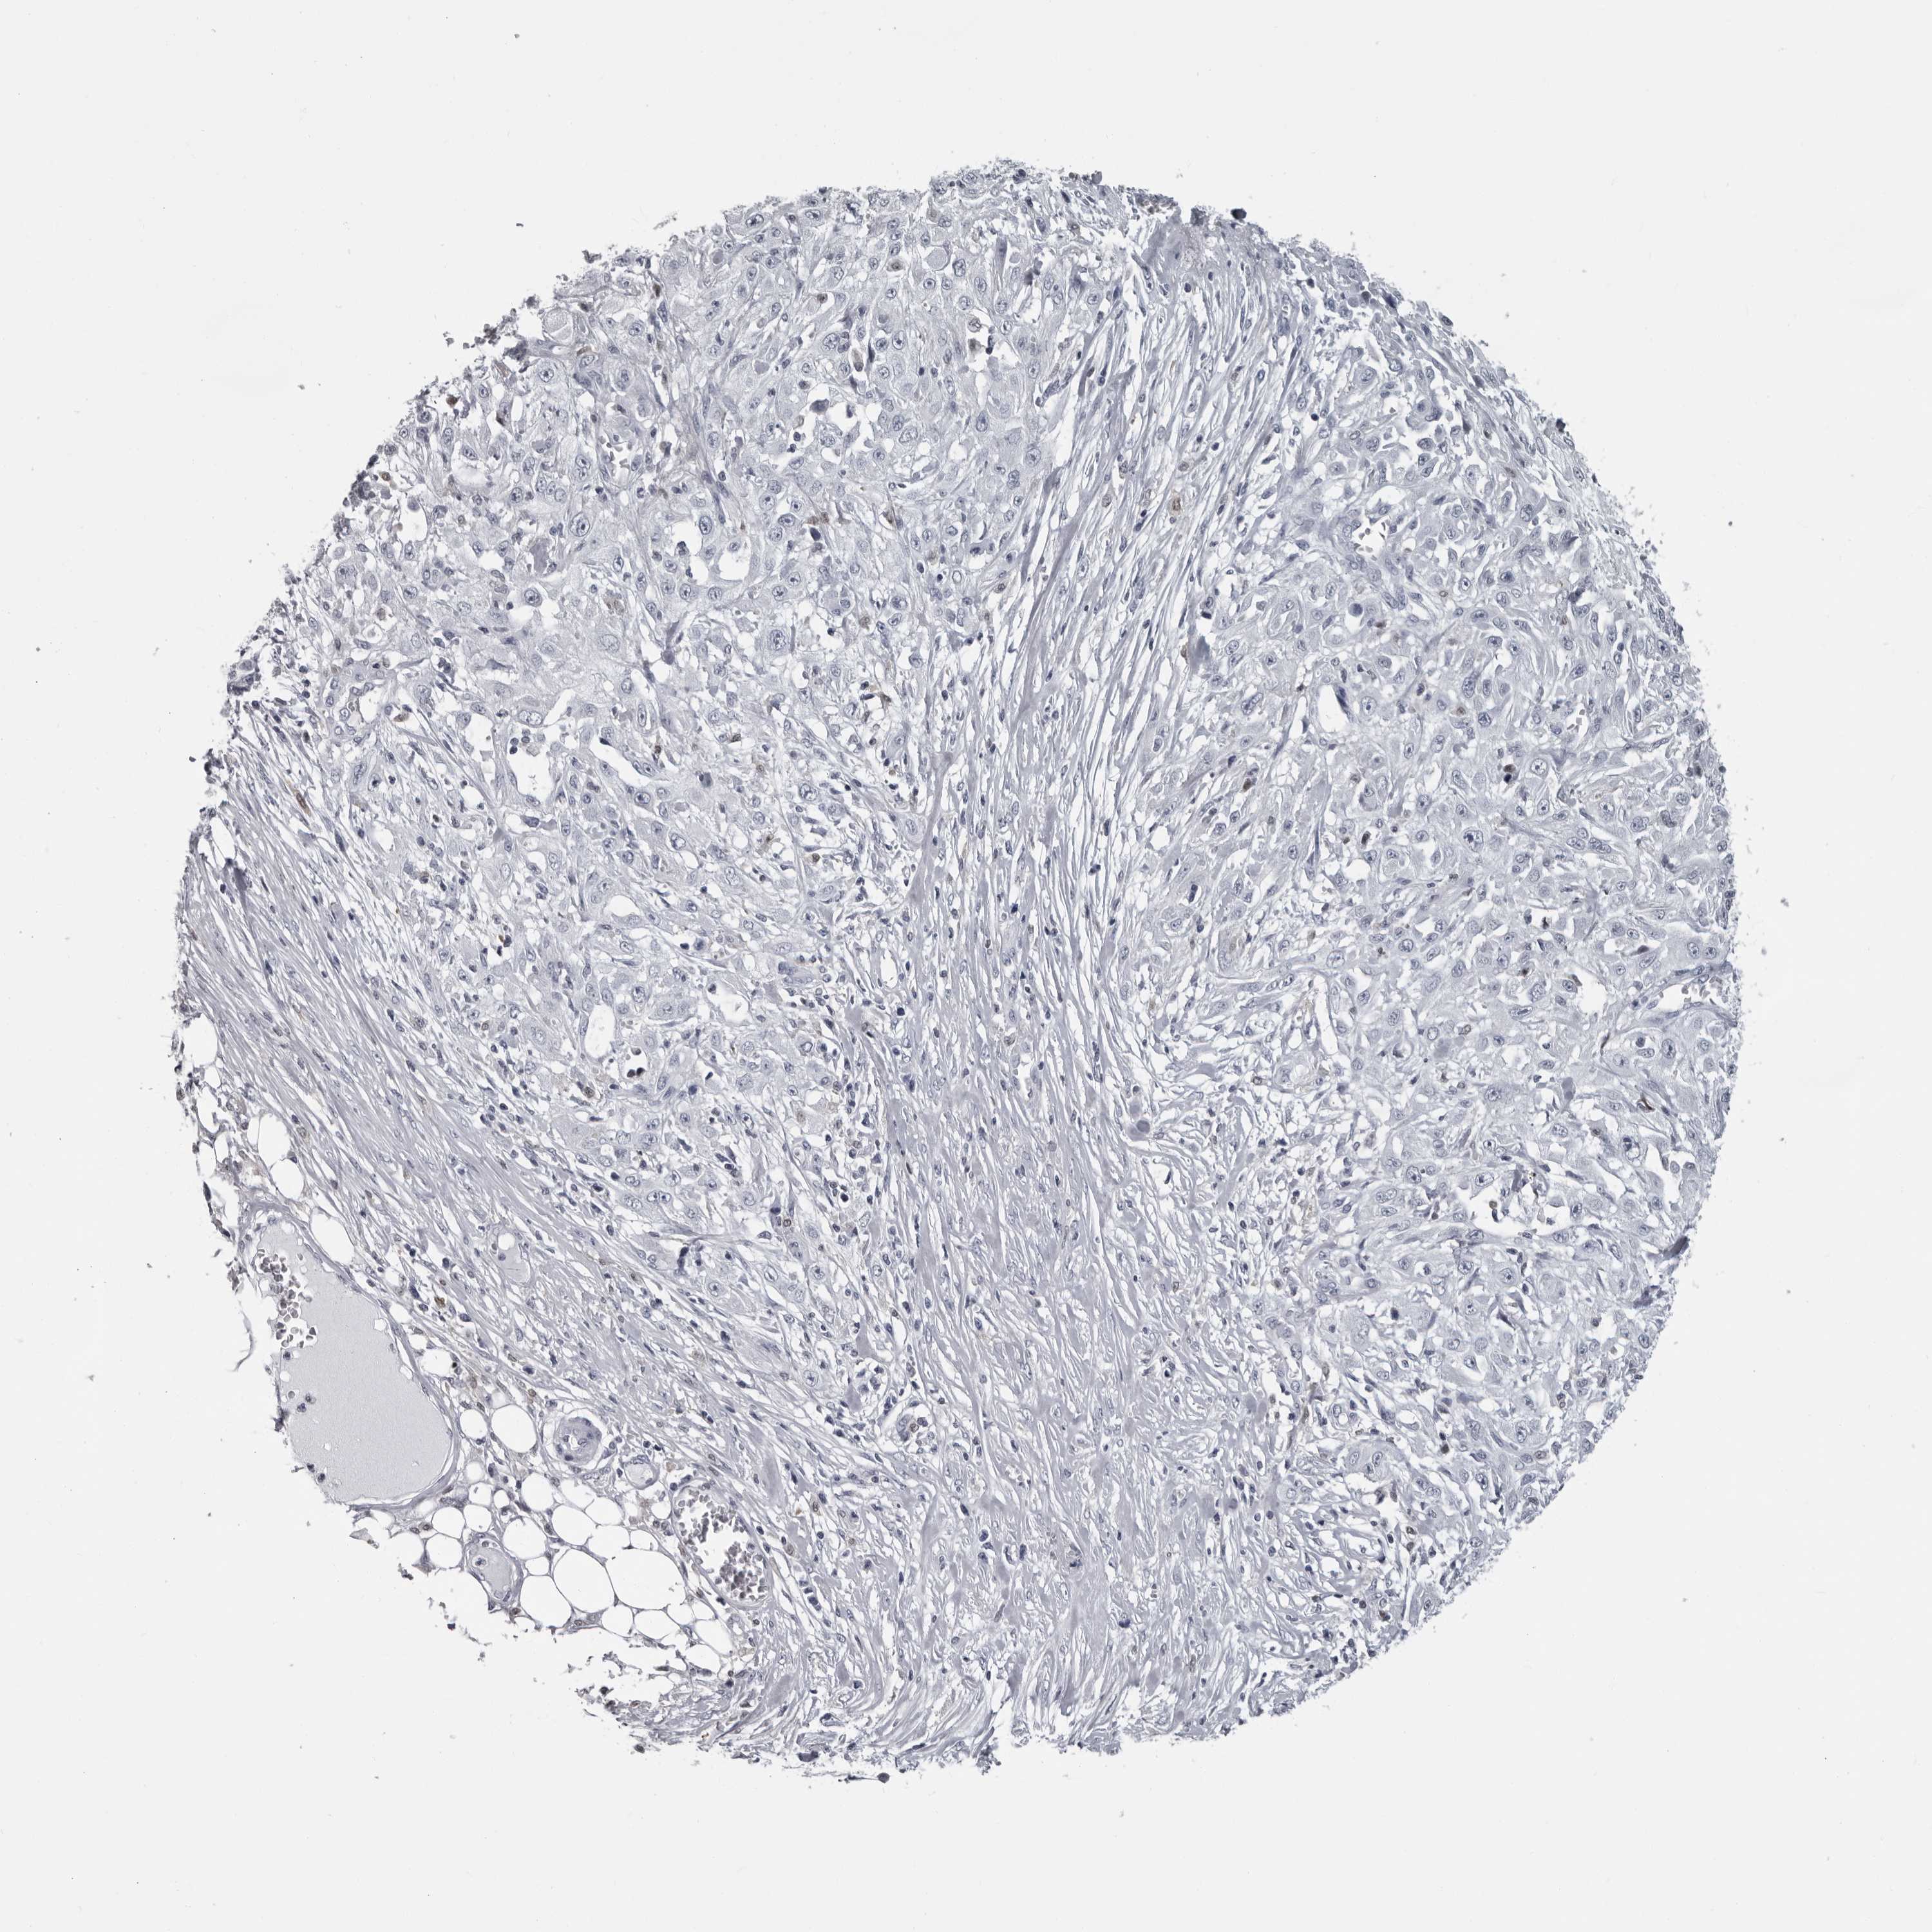

SKIN CANCER - Protein expressioni

A mouse-over function shows sample information and annotation data. Click on an image to view it in a full screen mode. Samples can be filtered based on level of antibody staining by selecting one or several of the following categories: high, medium, low and not detected. The assay and annotation is described here.

Each image is clickable and will lead to virtual microscopy that enables deeper exploration of all samples and also displays staining intensity scores, fraction scores and subcellular localization as well as patient and tissue information for each sample.

Antibody HPA028184

Staining

High

Medium

Low

Not detected

Intensity

Strong

Moderate

Weak

Negative

Quantity

>75%

75%-25%

<25%

None

Location

Nuclear

Cytoplasmic/membranous

Cytoplasmic/membranous,nuclear

Basal cell carcinoma